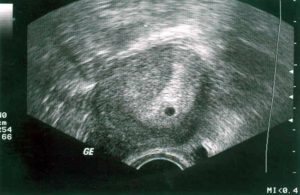

Три акушерские недели соответствуют одной неделе от зачатия. Зародыш ещё настолько мал, что его невозможно увидеть на ультразвуковом исследовании.

Но плодное яйцо ещё настолько мало, что его либо не видно, либо невозможно отличить от подобных структур в полости матки.

Основные изменения, которые видны при выполнении ультразвуковой диагностики, это утолщенный эндометрий. Зачастую величина внутренней слизистой оболочки составляет 15-20 мм. Но это значение может быть и меньше.

Визуализация матки на УЗИ может ничем не отличаться от картинки во второй фазе цикла.

По сути, в это период беременность уже есть, но отличить зиготу еще невозможно. Могут визуализироваться лишь косвенные признаки наступления зачатия, среди них:

- Гиперплазия эндометря.

- Место на слизистой с максимальным утолщением – это может указывать на подготовку места к внедрению зародыша.

Вывод. На третьей неделе гестации увидеть плод, а уж тем более зародыш еще не получиться. Даже плодное яйцо еще не визуализируется. Единственное что можно рассмотреть, так это то готовиться ли организм к имплантации зиготы или вот-вот начнутся месячные.